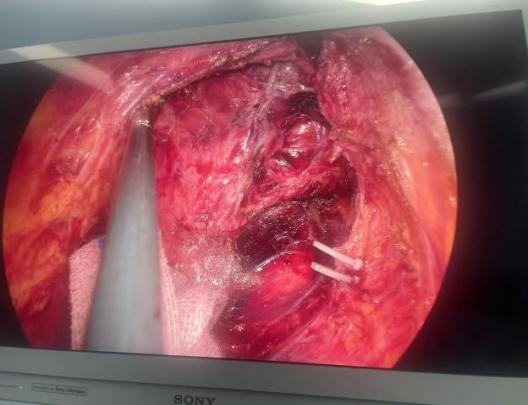

面对两位患者直肠腺癌的特殊病情,肿瘤位置紧贴肛门环的传统手术“禁区”,副主任朱盼盼依托“创想医生”APP进行四级手术术前MDT,确定手术方案为超低位直肠癌保肛根治术。术中严密解剖,经肛门外括约肌内侧分离直肠肠壁,既保留了肛门功能,同时切除更多的远端直肠(肛管)组织,将保肛距离推向极限低位。手术以最小的创伤完整地切除了肿瘤,更有效地保护了患者的正常生理功能。两名患者术后10日顺利出院。